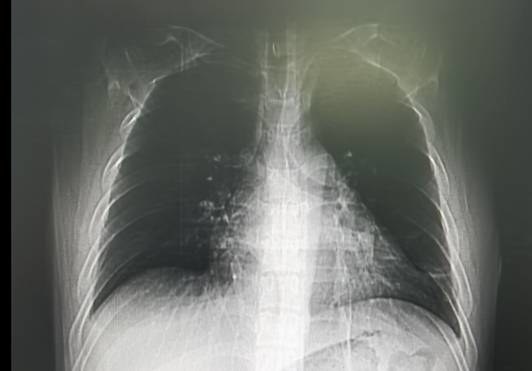

治疗前胸片:双肺多发渗出灶

治疗后胸片:渗出灶全部吸收